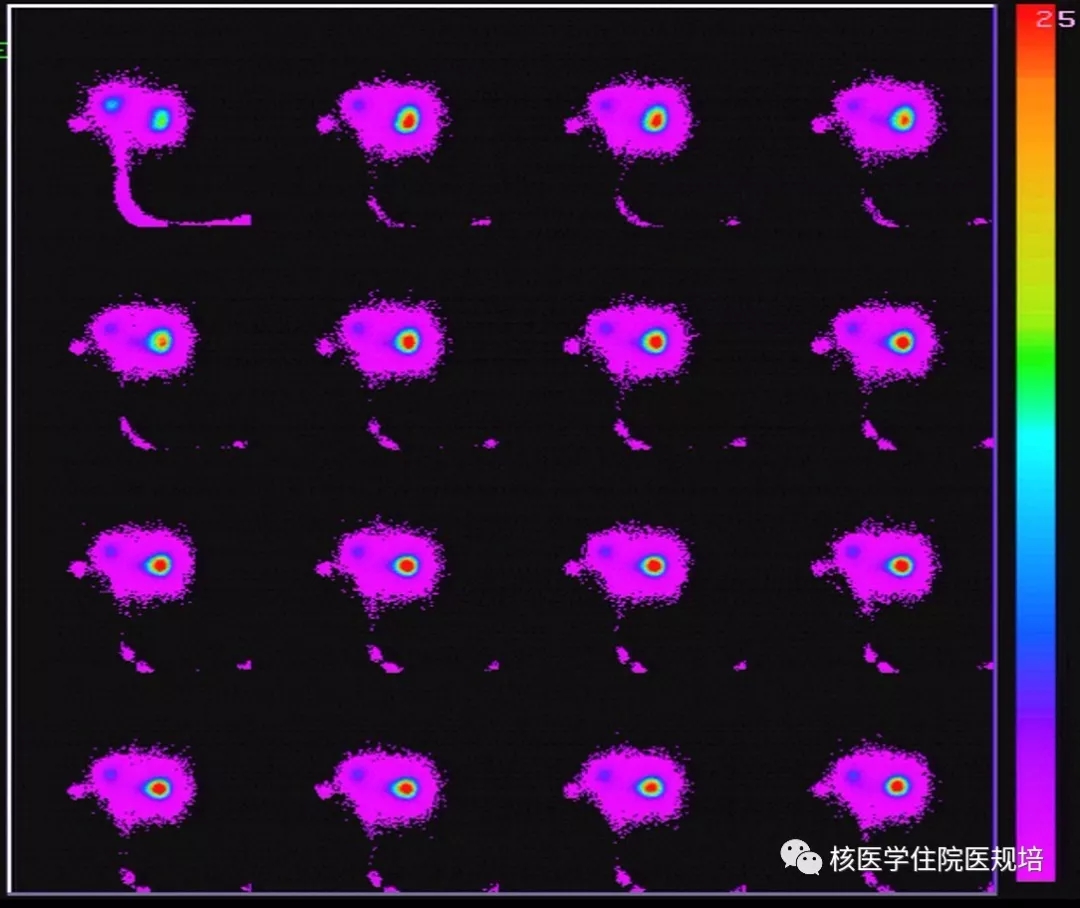

子宫输卵管造影(HSG)检查:经宫颈口注入造影剂顺利,宫腔形态大致正常,双侧输卵管走行可,通畅,盆腔内造影剂弥散良好。检查结论:子宫输卵管造影未见明显异常(图1)。

图1 子宫输卵管造影(HSG)检查

第1采集时相:常规子宫腔内插管,注入显像剂99mTcO4- (37MBq,1ml)后即刻以2s /帧行盆腔前位动态显像,采集时间60s。显像时间内双侧输卵管远端(卵巢)部位未见放射性聚集(图2)。

第2采集时相:继续以1min /帧行盆腔前位动态显像,采集时间30min。双侧输卵管远端(卵巢)部位始终未见放射性聚集,阴道内见较多放射性聚集(图3)。

第3采集时相:再次缓慢向宫腔内注入显像剂99mTcO4-(37MBq ,10ml),同时以5s/帧行盆腔前位动态显像。可见双侧输卵管远端(卵巢)及周围放射性聚集明显增加,周围弥散良好(图4)。